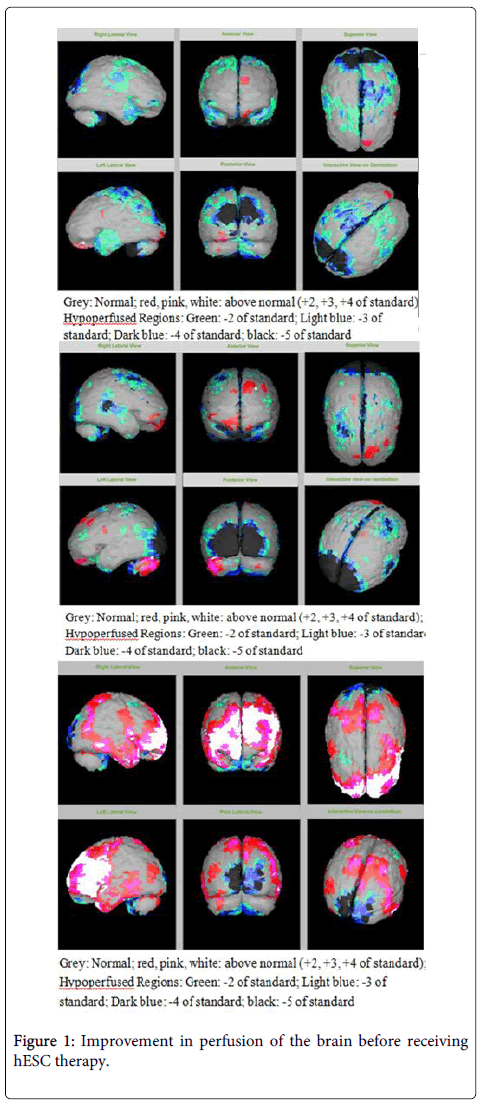

該患者的SPECT掃描如圖1和2所示。

圖1:接受hESC治療前大腦灌注的改善。

SPECT掃描

在研究開(kāi)始和結(jié)束時(shí),23名患者接受了SPECT掃描。在枕葉或額葉或雙葉中觀察到灌注不足。23例接受SPECT掃描的患者中,5例患者表現(xiàn)為枕葉灌注不足,7例患者表現(xiàn)為額葉灌注不足,11例患者表現(xiàn)為枕葉和額葉灌注不足。

總體而言,治療結(jié)束時(shí),2名患者的灌注正常,18名患者(12名男性和6名女性患者)顯示灌注顯著改善(>60%),3名患者顯示灌注中度改善(30-60%)。大多數(shù)在接受hESC治療前額葉和枕葉嚴(yán)重低灌注的患者在接受 hESC 治療后情況有所改善。23名可獲得SPECT掃描報(bào)告的患者的GMFCS評(píng)分在hESC治療后有所改善(表2)。